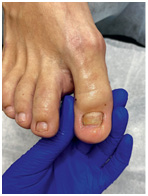

Хирург не заботится об эстетической стороне вопроса. Ему важно решить проблему, чтобы вы больше не испытывали дискомфорт. Часто после хирургического лечения ноготь меняет форму, становится менее красивым – к этому нужно быть готовым.

Иллюстрация к книге — Подология понятно. Важен каждый шаг. Справочник по проблемам подологии для клиентов и мастеров эстетики [i_269.jpg]

Иллюстрация к книге — Подология понятно. Важен каждый шаг. Справочник по проблемам подологии для клиентов и мастеров эстетики [i_270.jpg]

Иллюстрация к книге — Подология понятно. Важен каждый шаг. Справочник по проблемам подологии для клиентов и мастеров эстетики [i_271.jpg]

Иллюстрация к книге — Подология понятно. Важен каждый шаг. Справочник по проблемам подологии для клиентов и мастеров эстетики [i_272.jpg]

Результат работы за 5 месяцев: подолог использовал крючковые коррекционные системы, а хирург сделал пластику внутреннего бокового валика (из-за хронических воспалений боковой валик стал гипертрофированным и давил на ноготь, от чего клиент испытывал постоянный дискомфорт)